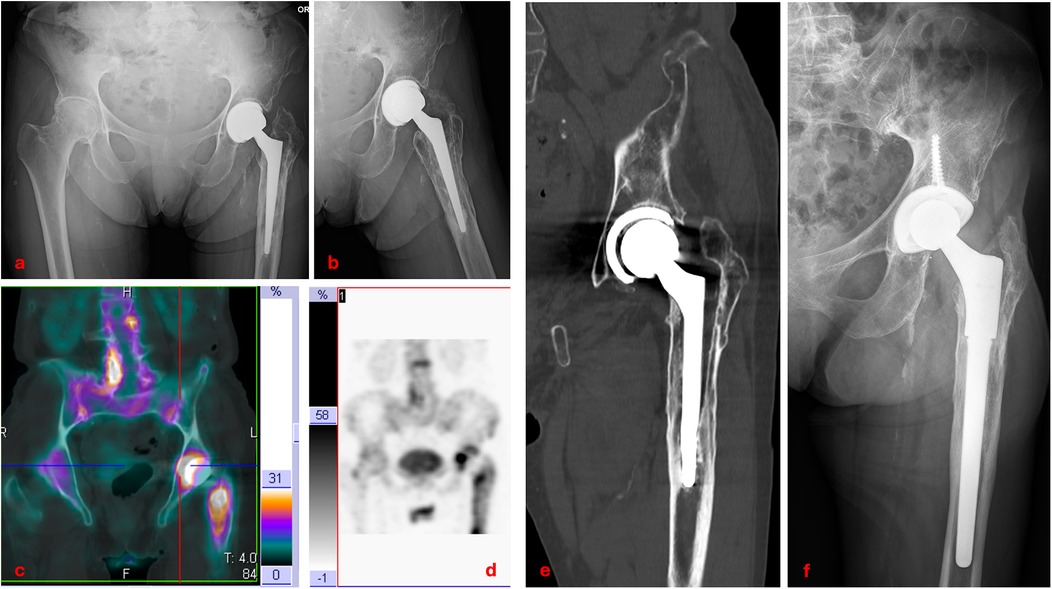

The complication profile in our series was low, with an overall failure rate of 10.5% over nearly two decades. Aseptic loosening (Figure 5), the most frequent cause of revision in DDH THA, occurred in three cases (5.2%), a rate that falls within the 2%–10% range reported in long-term series [13, 16, 20]. Notably, one acetabular component failed within 12 days postoperatively, suggesting primary fixation problems rather than biological failure. Deep infection occurred in one case (1.8%), which is consistent with the 0.5%–2% incidence generally reported for primary THA [22]. In the literature, dislocation rates for THA in DDH vary widely: Mortazavi et al. [23] found a rate of 12% in a series of 171 patients, while Ding et al. [24] documented dislocation in 22 of 524 hips (4.2%) treated for dysplasia. The dislocation rate in our study was 1.8%, which may reflect meticulous preoperative planning and careful restoration of offset, version, and soft-tissue tension. The single case of metallosis, presenting with pseudotumor formation 15 years after surgery, highlights the importance of long-term follow-up, especially where metal debris from modular junctions may accumulate over time.

Figure 5

A series of medical images showing a hip joint replacement. Image a: X-ray of the pelvis frontal view with hip prosthesis. Image b: X-ray of the right hip lateral view with prosthesis. Image c: PET scan with highlighted areas, showing differing densities. Image d: Blurry PET scan focused on the hip region. Image e: CT scan of the hip displaying the prosthetic joint in detail. Image f: X-ray of the right hip with an updated prosthetic model.

Figure 5. Clinical case of aseptic loosening of total hip arthroplasty: anteroposterior and lateral radiographs (a,b); baseline three-phase bone scintigraphy with 99mTc showing increased uptake around the prosthesis (c,d); coronal CT scan demonstrating loosening of both the femoral stem and acetabular cup (e); postoperative radiograph after revision surgery with a new modular stem (f).